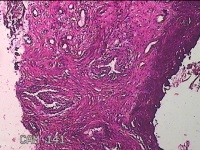

宫颈锥切物

性别

女

年龄

36岁

临床诊断

宫颈CIN2 宫颈乳头病毒感染

一般病史

检查发现CIN21个月。

标本名称

大体所见

灰白粉红色组织5.5x1.3x0.8cm一块,表面糜烂,切面灰白粉红色,质软,另有灰白粉红色组织2.3x2x0.3cm一堆,表面糜烂,切面灰白粉红色,质中。